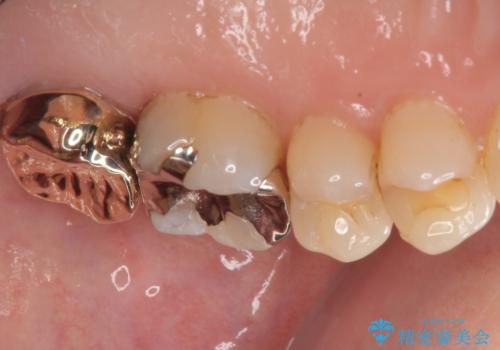

放置した奥歯のむし歯 ゴールドクラウン補綴治療

- 上の奥歯を放置してしまったとのことで来院された患者様です。

虫歯が大きいのでクラウンによる治療が必要となりますが、咬む力がとても強いために、歯と同じ堅さであるPGAクラウン(白金加金合金クラウン)をお勧めしました。

上の奥歯であることから、審美性よりも機能性を優先され、ゴールドクラウンを選択されました。

装着後の違和感など一切なく、見た目もほとんど気にならないとのことで、患者様には大変満足していただけました。